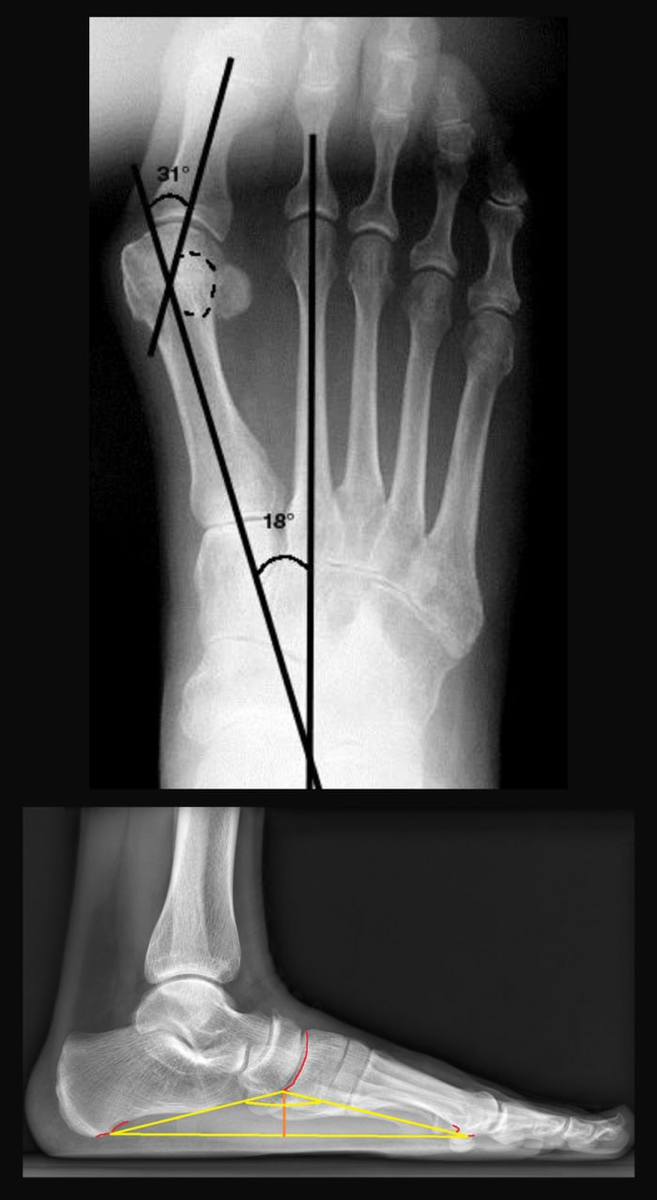

Если посмотреть на рентген, становится наглядно видно разницу.

В норме угол между первой и второй плюсневыми костями составляет 6–10 градусов. При hallux valgus он увеличивается, например до 18 градусов и более.

В большинстве случаев коррекция выполняется с помощью остеотомий, то есть искусственных переломов. Их задача уменьшить угол между первой и второй плюсневыми костями и выпрямить большой палец.